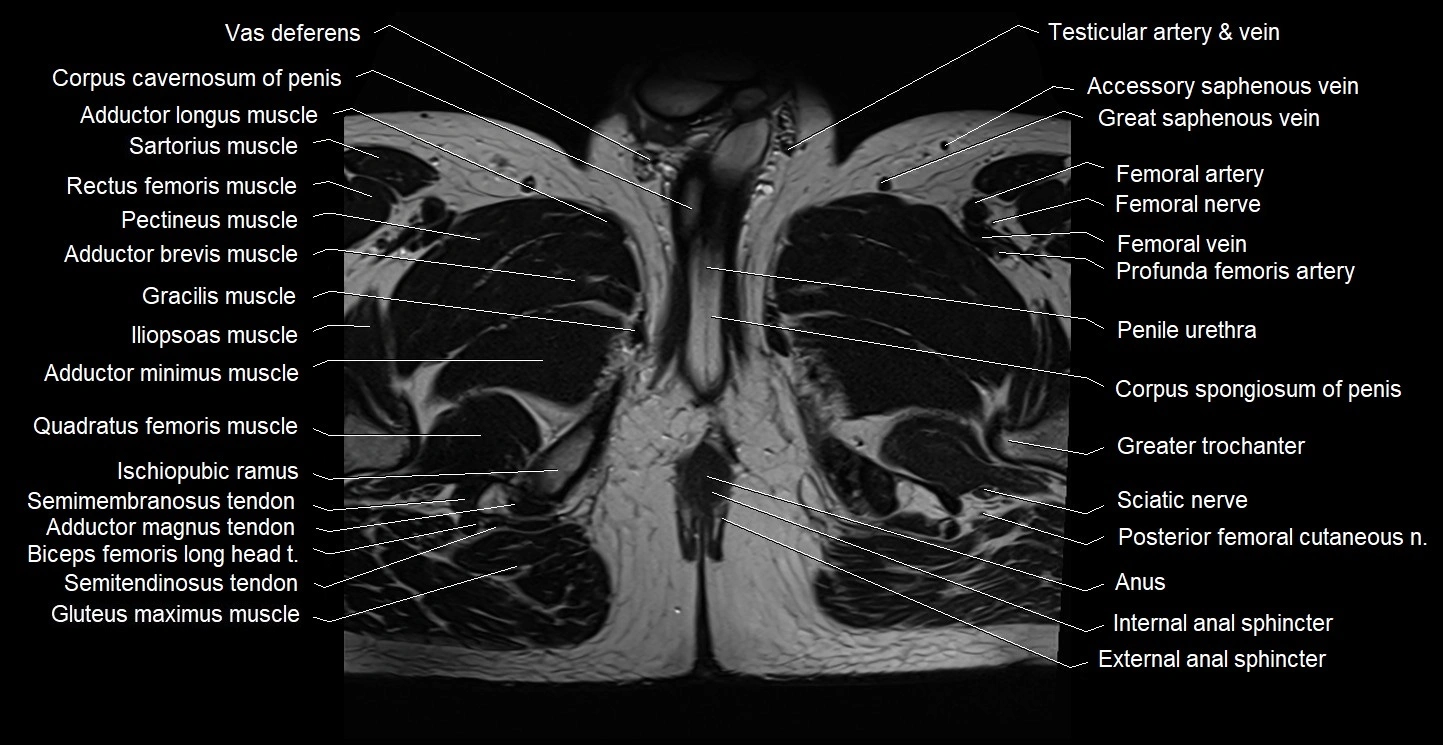

- Adductor brevis muscle

- Adductor longus muscle

- Adductor magnus muscle

- Adductor minimus muscle

- External anal sphincter

- Gracilis muscle

- Iliopsoas muscle

- Internal anal sphincter

- Ischiopubic ramus

- Penile urethra

- Posterior femoral cutaneous nerve

- Quadratus femoris muscle

- Sciatic nerve